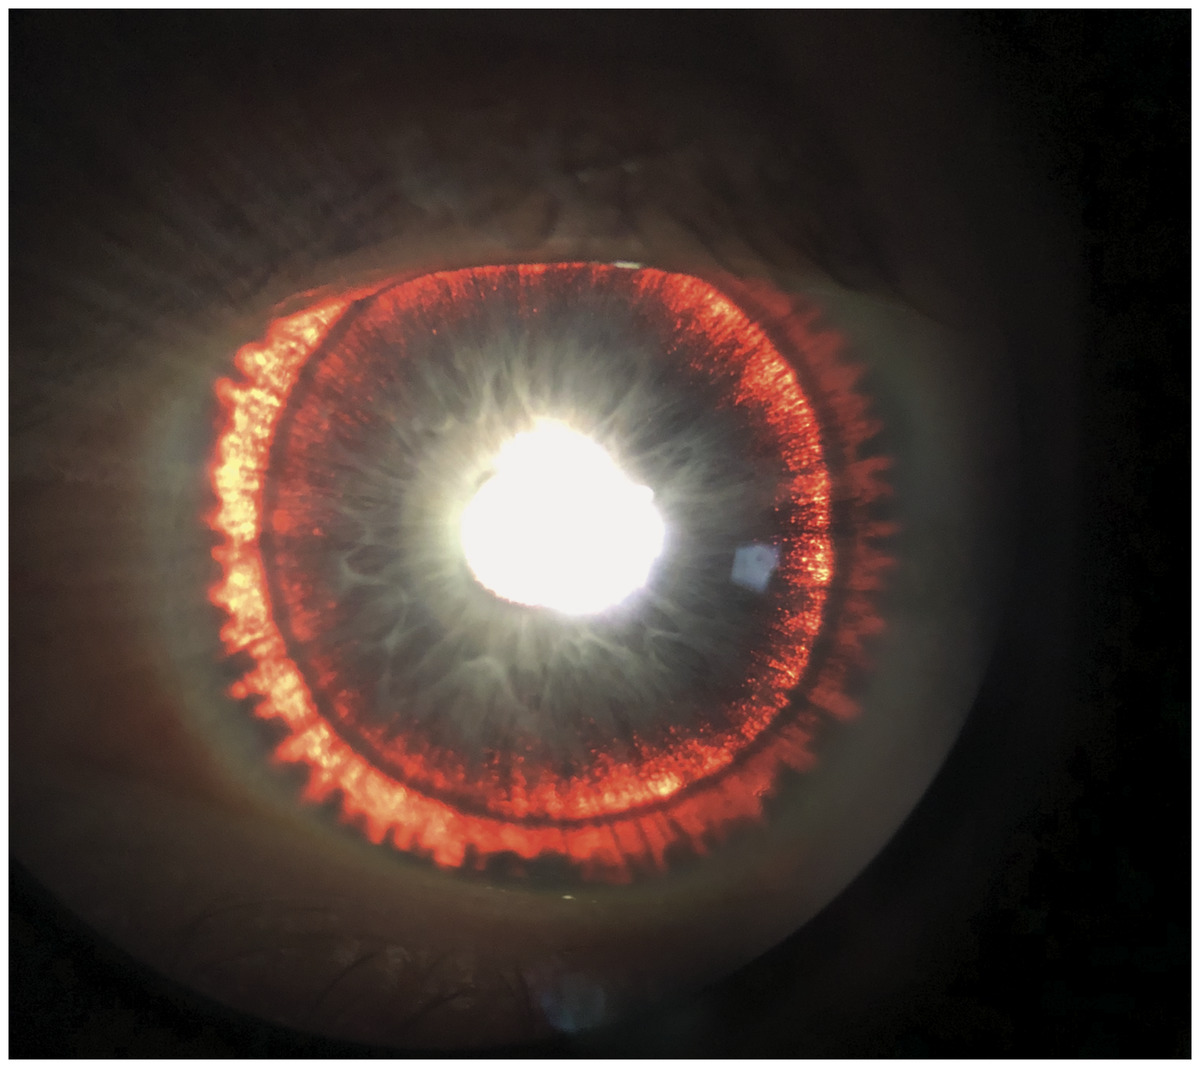

홍채를 관찰하면 방사상 모양으로 투시결손이 나타납니다.

즉, 홍채에서 색소가 탈락한 부분에는 빛의 투과가 많아 지므로,

그 부분이 투명하게 관찰 되게됩니다.

또한 홍채 뒷면에서 유리된 색소들이 전방을 떠다니다가 전안부(anterior segment)에 이곳저곳 침착됩니다.

전방각경 검사를 하면 섬유주 전반에 걸쳐

짙고 균일한 어두운 갈색의 색소띠가 관찰됩니다.